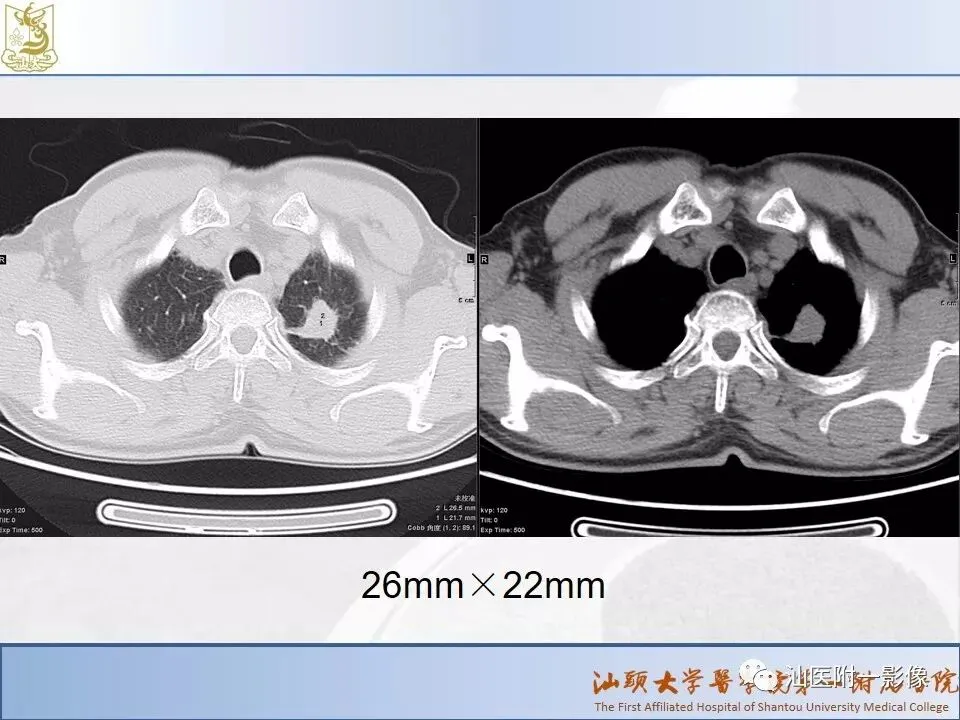

肺结节分类、处理及浅识肺结节分类影像报告和数据系统(Lung-RADS)

来源:汕医附一影像

说明:本课程病例主要来源于本院病例及参考资料,

无涉及病人隐私,仅做教学用途。